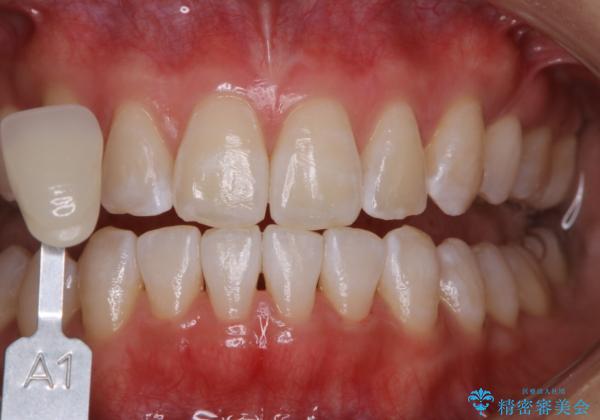

- オフィスホワイトニング希望で1日で白くしたいとのことでした。

オフィスホワイトニングのエクセレントコース(¥29700)を行いました。